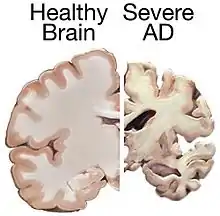

Alzheimer's disease is characterised by loss of neurons and synapses in the cerebral cortex and certain subcortical regions. This loss results in gross atrophy of the affected regions, including degeneration in the temporal lobe and parietal lobe, and parts of the frontal cortex and cingulate gyrus.[84] Degeneration is also present in brainstem nuclei particularly the locus coeruleus in the pons.[85] Studies using MRI and PET have documented reductions in the size of specific brain regions in people with Alzheimer's disease as they progressed from mild cognitive impairment to Alzheimer's disease, and in comparison with similar images from healthy older adults.[86][87]

Both Aβ plaques and neurofibrillary tangles are clearly visible by microscopy in brains of those with Alzheimer's disease,[88] especially in the hippocampus.[89] However, Alzheimer's disease may occur without neurofibrillary tangles in the neocortex.[90] Plaques are dense, mostly insoluble deposits of beta-amyloid peptide and cellular material outside and around neurons. Tangles (neurofibrillary tangles) are aggregates of the microtubule-associated protein tau which has become hyperphosphorylated and accumulate inside the cells themselves. Although many older individuals develop some plaques and tangles as a consequence of aging, the brains of people with Alzheimer's disease have a greater number of them in specific brain regions such as the temporal lobe.[91] Lewy bodies are not rare in the brains of people with Alzheimer's disease.[92]